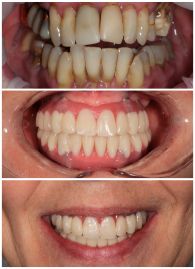

УЛЫБАЮСЬ СВОБОДНО И ОТКРЫТО

Восстановление широкой улыбки в день операции. Больше не надо прикрывать рот ладонью!

Клинические случаи

Максимальная эстетика и функция в день операции